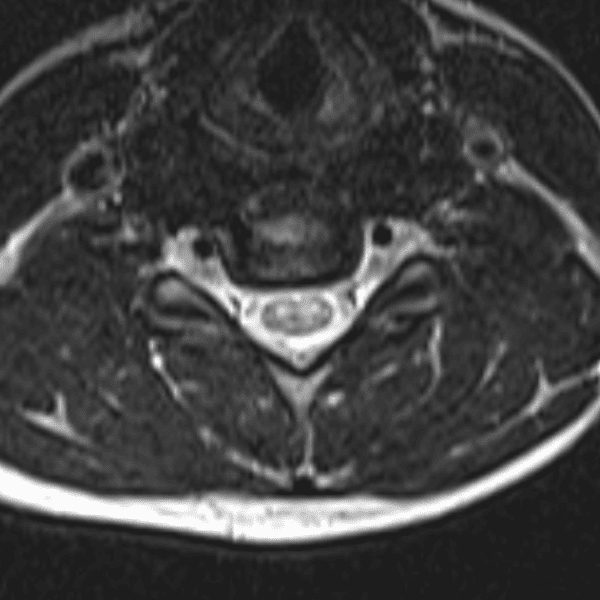

Simulates call by including subtle or difficult cases and some normals.

35 cases